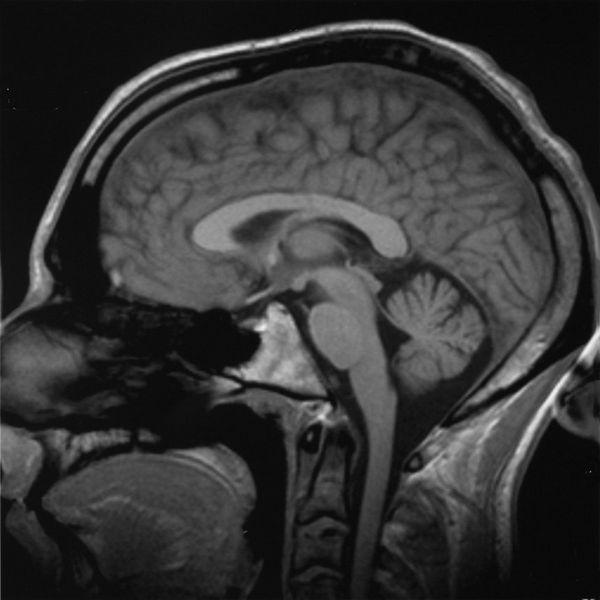

El estudio tomográfico es ampliamente utilizado en diversas especialidades médicas, desde la neurología hasta la oncología. Una de sus principales aplicaciones es en la evaluación del sistema nervioso central, permitiendo detectar lesiones cerebrales, accidentes cerebrovasculares, tumores, hemorragias intracraneales y malformaciones congénitas. En traumatología, es esencial para examinar fracturas complejas, lesiones en órganos internos y daños musculoesqueléticos.

- Tomografía craneal: Se centra en el análisis del encéfalo y estructuras craneanas, útil para evaluar traumatismos, tumores, edemas o sangrados.